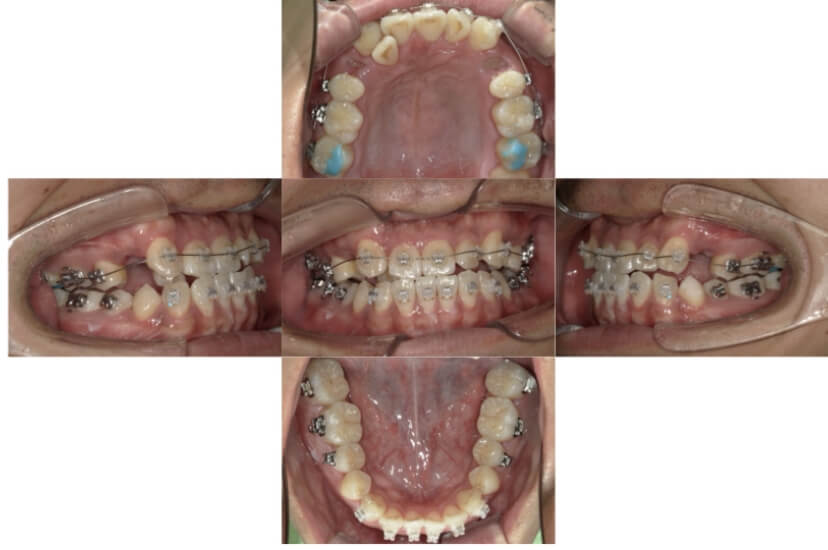

上下顎叢生(上下の前歯のガタガタ)および上顎前突のケースです。

装置はラビアル(上下表側)で、左上C(乳歯)と右上および下顎両側の小臼歯を抜歯(計4本)を行っています。抜歯したスペースを利用し、上下の前歯の後方移動と叢生(ガタガタ)の改善を行っています。また、上顎前突改善のため歯科用アンカースクリューを使用し、上顎歯列全体の後方移動をおこないました。

主訴 上下の前歯のガタガタと出っ歯を治したい。

年齢・性別 16歳 男性

お住まいの地域 神奈川県川崎市

治療方針 抜歯スペースを利用して上下前歯の叢生(ガタガタ)の改善、上顎歯列の遠心移動

抜歯部位 上顎右側第一小臼歯、上顎左側乳犬歯、下顎両側第一小臼歯

使用装置 ラビアル(上下表側)、顎間ゴム、歯科用アンカースクリュー

治療期間 2年8か月

治療回数 21回

BEFORE

AFTER